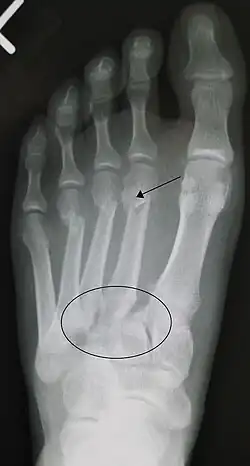

An X-ray of a Lisfranc injury

Lisfranc fracture (marked by the oval). This case also has fractures of the distal second (marked by the arrow), third, and fourth metatarsal bones.

In a high energy injury to the midfoot, such as a fall from a height or a motor vehicle accident, the diagnosis of a Lisfranc injury should, in theory at least, pose less of a challenge. There will be deformity of the midfoot and X-ray abnormalities should be obvious. Further, the nature of the injury will create heightened clinical suspicion and there may even be disruption of the overlying skin and compromise of the blood supply. Typical X-ray findings would include a gap between the base of the first and second toes.[8] The diagnosis becomes more challenging in the case of low energy incidents, such as might occur with a twisting injury on the racquetball court, or when an American Football lineman is forced back upon a foot that is already in a fully plantar flexed position. Then, there may only be complaint of inability to bear weight and some mild swelling of the forefoot or midfoot. Bruising of the arch has been described as diagnostic in these circumstances but may well be absent.[9] Typically, conventional radiography of the foot is utilized with standard non-weight bearing views, supplemented by weight-bearing views which may demonstrate widening of the interval between the first and second toes, if the initial views fail to show abnormality. Unfortunately, radiographs in such circumstances have a sensitivity of 50% when non-weight bearing and 85% when weight-bearing, meaning that they will appear normal in 15% of cases where a Lisfranc injury actually exists.[10] In the case of apparently normal x-rays, if clinical suspicion remains, advanced imaging such as magnetic resonance imaging (MRI) or computed tomography (CT scan) is a logical next step.[11]